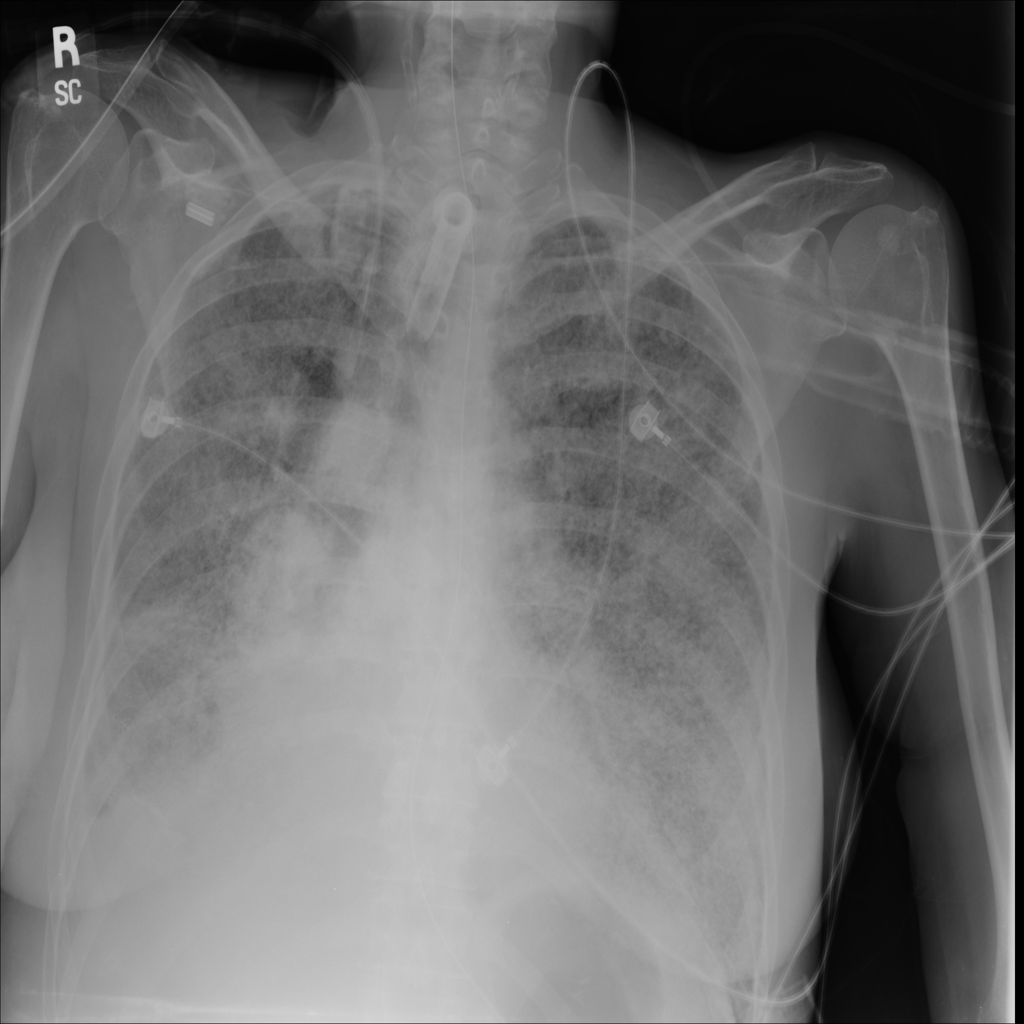

PAT-4639 · IMG-024Mass

PAT-4639 · IMG-024

AP